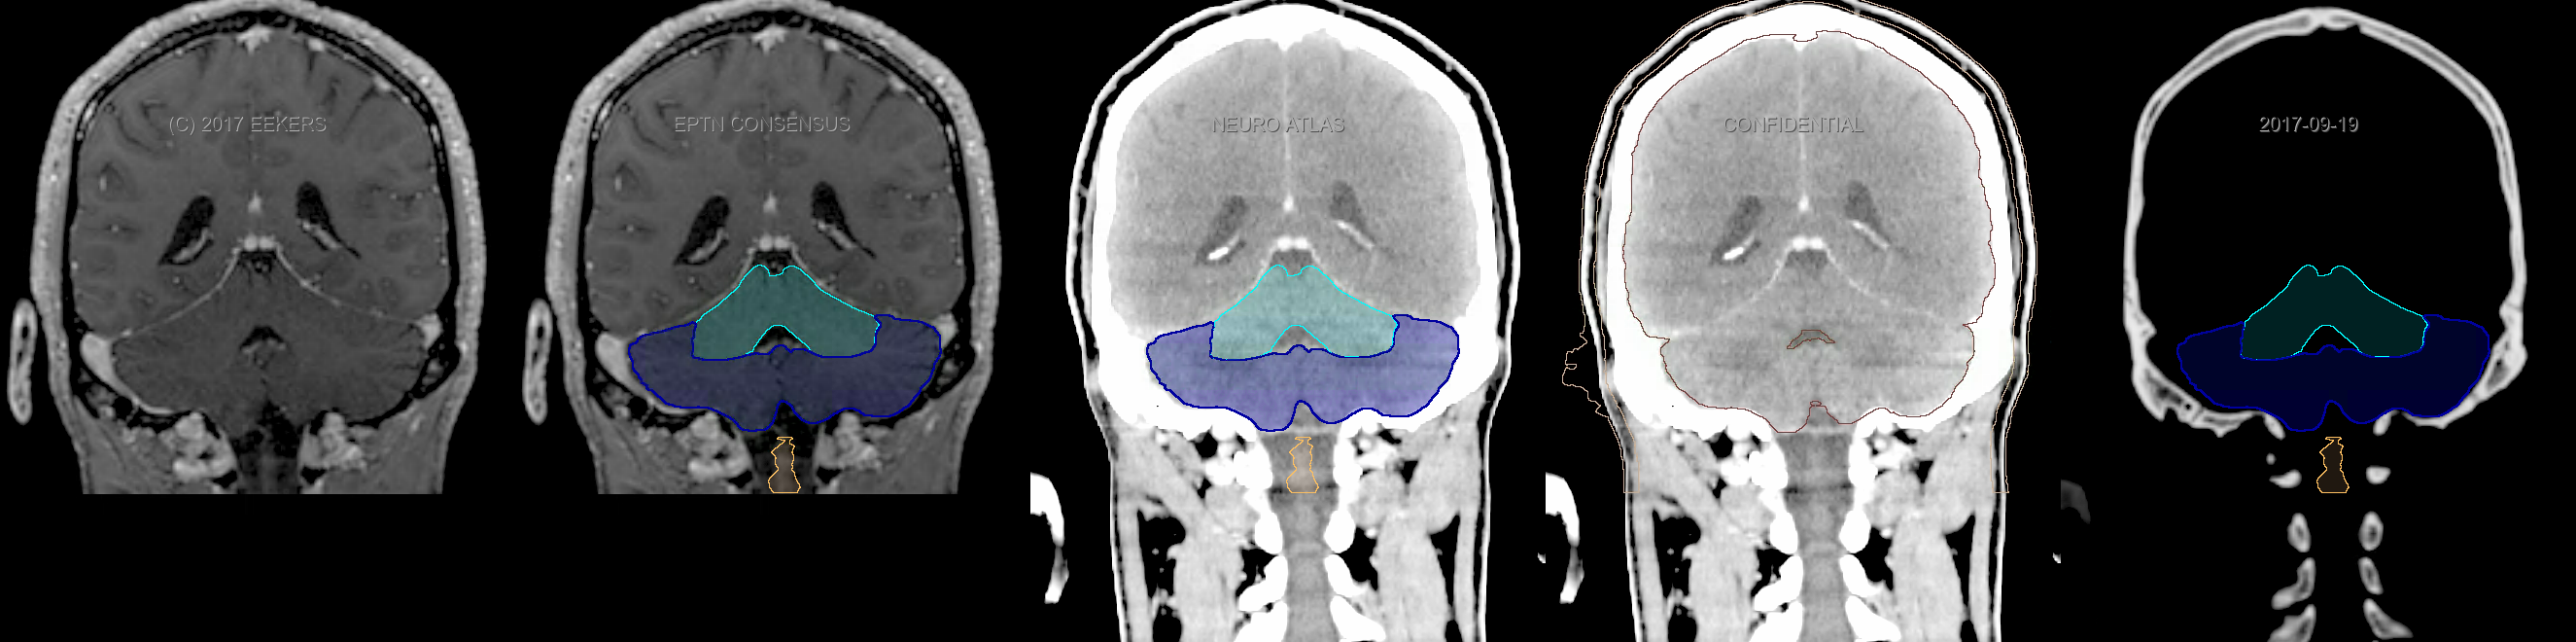

Eekers et al. have published an international neurological atlas for contouring of organs at risk in consensus with the European Particle Therapy Network (EPTN). The purpose of this consensus atlas is to decrease inter- and intra-observer variability in delineating OARs relevant for neuro-oncology. We propose this atlas is used in photon and particle therapy in order to derive consistent dosimetric data. When required this atlas will be updated according to new insights.

Included are all OARs known to be relevant for radiation-induced toxicity in neuro-oncology: brain, brainstem, cochlea, vestibulum & semicircular canals, cornea, lens, retina, lacrimal gland, optic nerve, chiasm, pituitary, hippocampus and skin. A new OAR relevant for neuro-cognition, the posterior cerebellum is also included.

Three-dimensional delineation of the fifteen consensus OARs for neuro-oncology are shown on CT and 3 Tesla (3T) MR images (slice thickness 1 mm with intravenous contrast agent). All are presented in transversal, sagittal and coronal view.

From left to right: MR without structures, MR with structures, CT (WW/WL 120/40) with structures, CT (WW/WL 120/40) with Brain and Brainstem Surface, CT (WW/WL 1500/120)with structures